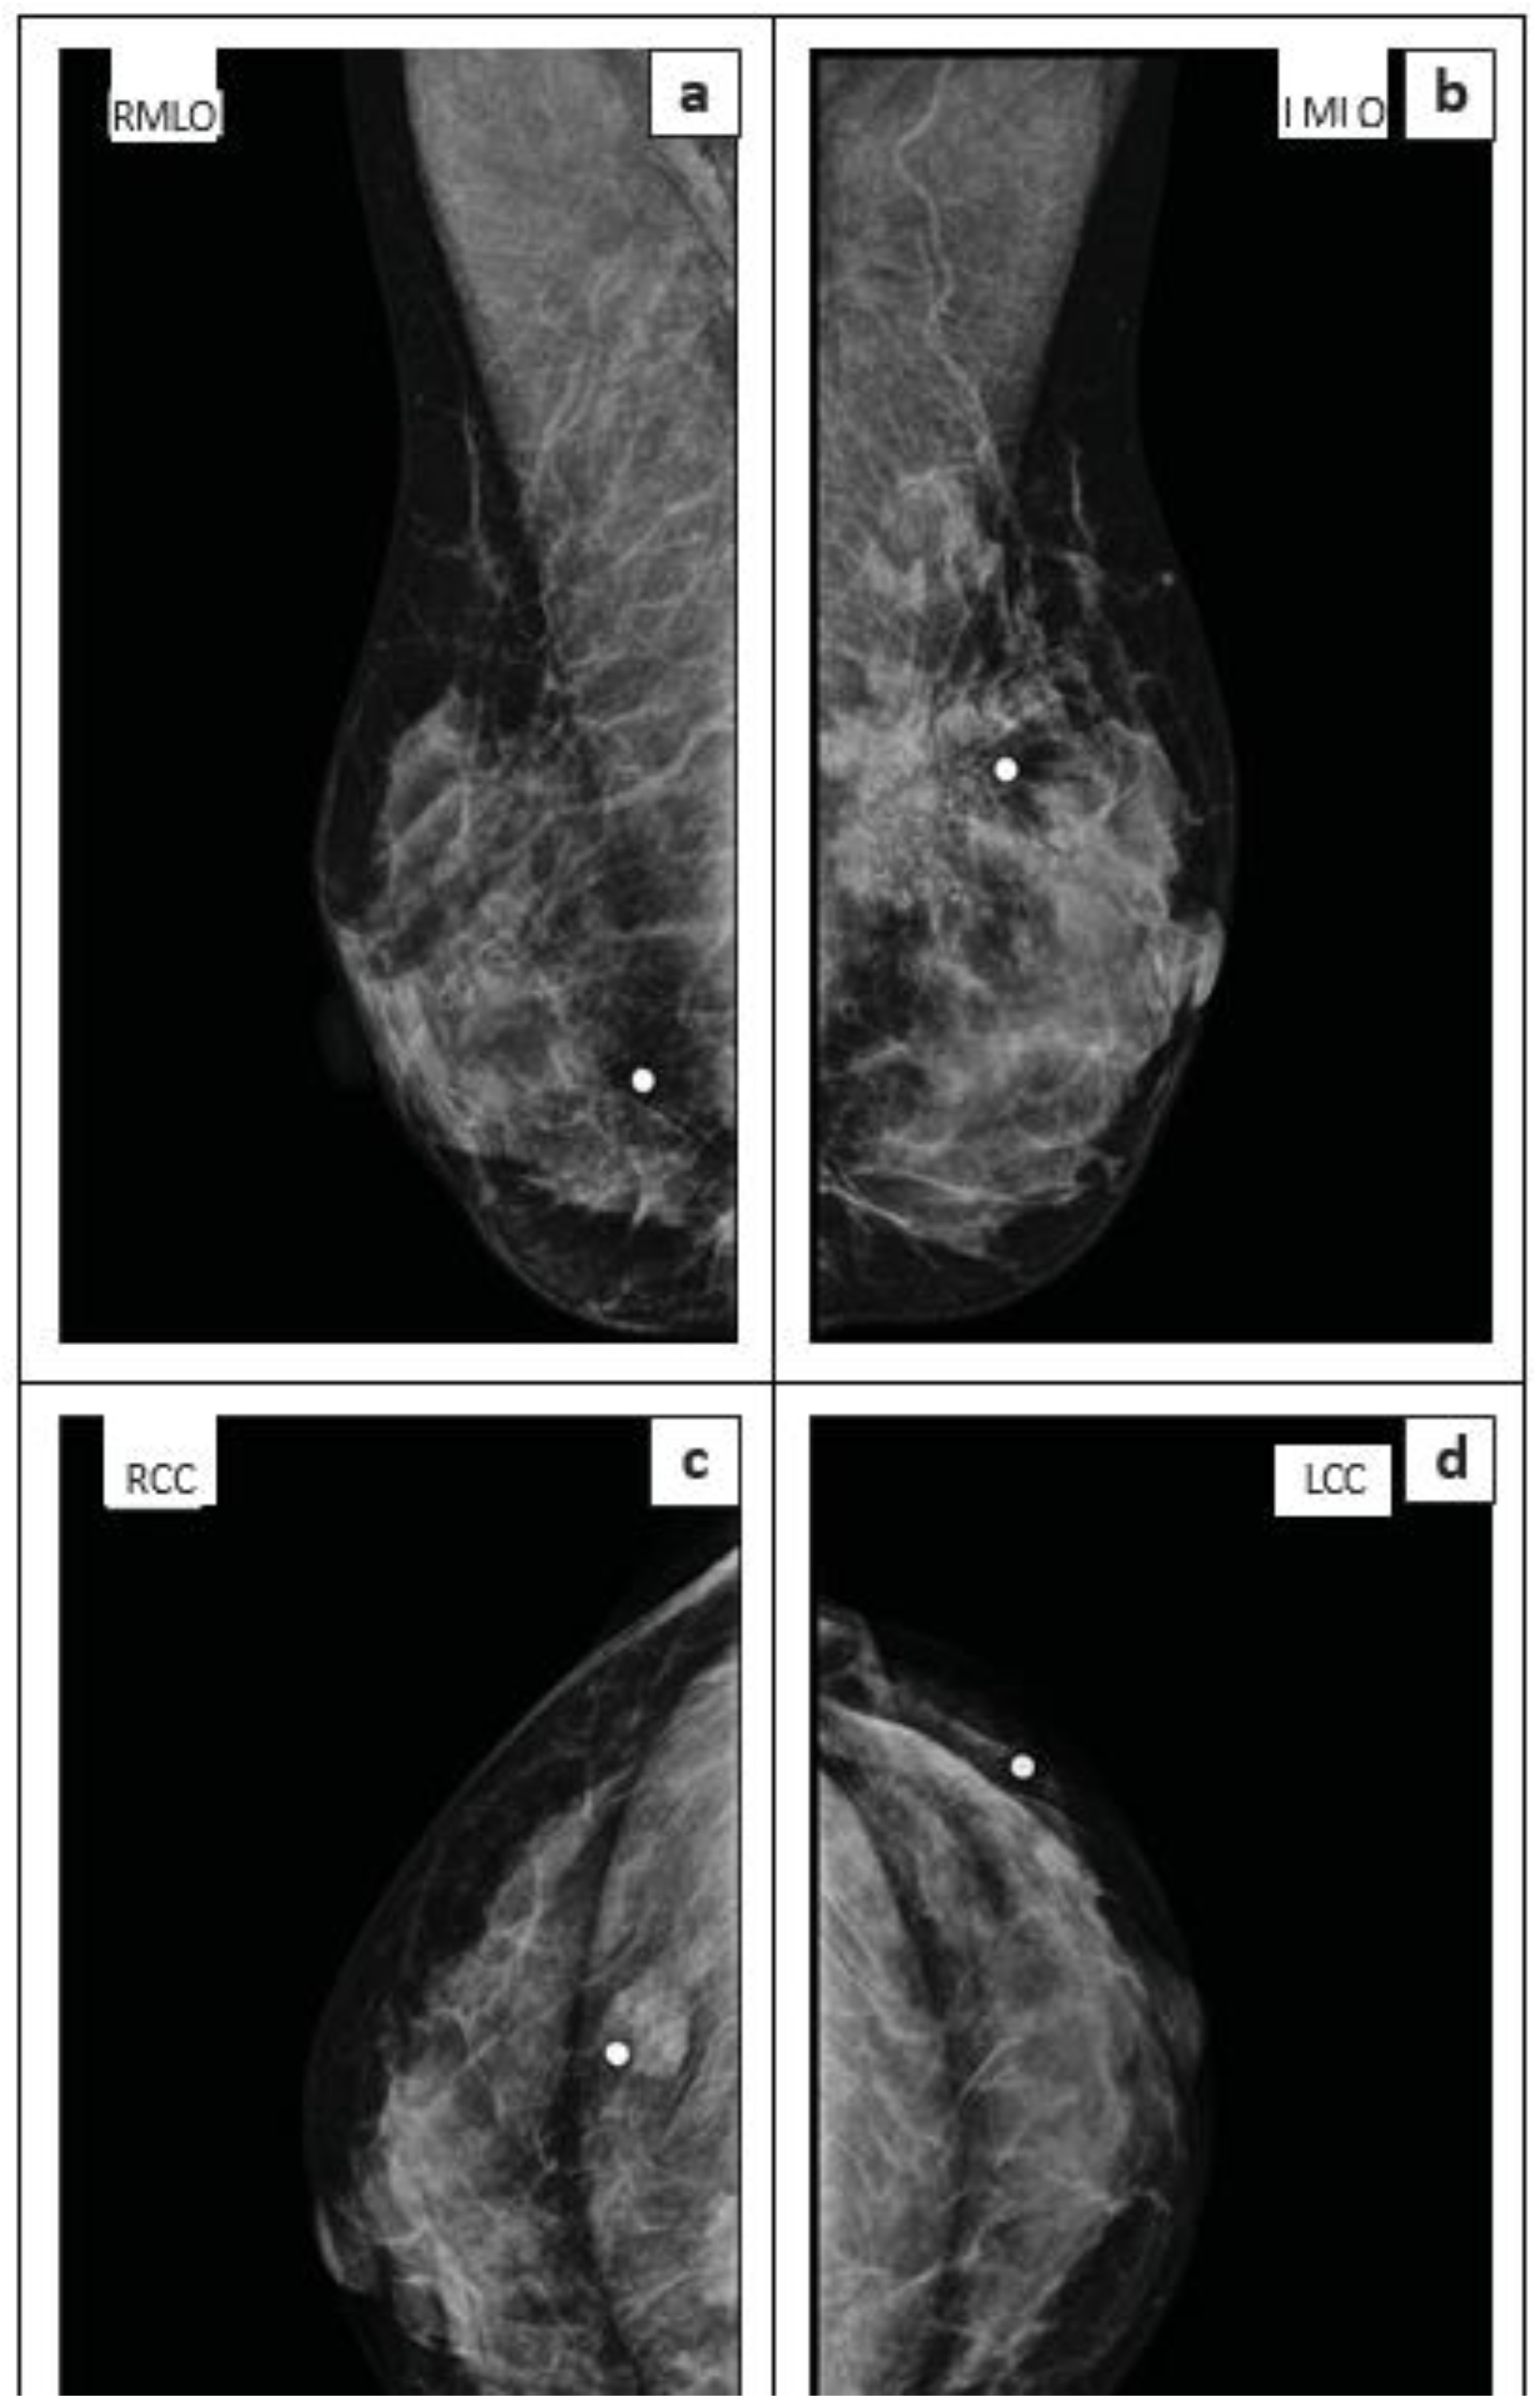

Sample mammogram images (shown in Figure 2), including the right mediolateral oblique (MLO) (a), left MLO (b), right craniocaudal (CC) (c), and left CC (d) views, reveal bilateral breast lumps, as indicated by skin markers at the palpable lesion sites.

In the right breast’s central lower quadrant, a focal soft tissue density is present, accompanied by pleomorphic calcifications. Correspondingly, the ultrasound of this lesion showed a hypoechoic appearance with poorly defined margins and posterior shadowing.

The left breast’s upper outer quadrant displays a larger, more concerning mass: a soft tissue density with spiculated margins, architectural distortion, and pleomorphic calcifications. Ultrasound confirmed that this lesion was also hypoechoic, with poorly defined margins and posterior shadowing.